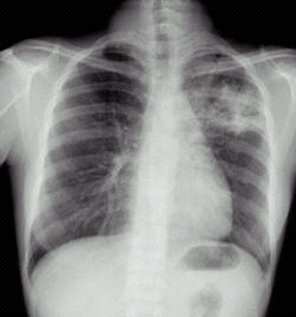

03卷-3.病史:男性,34歲,咳嗽、無痰半月,伴低熱。診斷(本題滿分2.00分)

左上浸潤型肺結(jié)核

本題答案:C

題目解析:【該題針對(duì)“X線-浸潤型肺結(jié)核”知識(shí)點(diǎn)進(jìn)行考核】